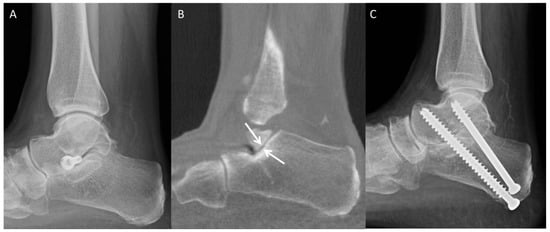

4.1. Accessory Navicular Resection

4.2. Cheilectomy